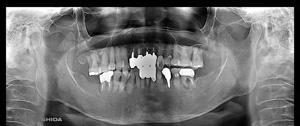

@@R.S‚³‚ñ@56Î —«  ‘åŠw‹³Žö @Žèp“ú@‚Q‚O‚O‚W”N ‚QŒŽ ‚X“úi“yj@㉺Š{  ƒm[ƒxƒ‹ƒKƒCƒhŽg—p@Ö¬“à’ÁÖ@•¹—p@@@

@@@@@ãŠ{  All on ‚U@‘¦Žž‰Ád@@

@@@@@@@@@@@@@ Rpl Tapered Rp  ‚P‚O mm(‚U–{)

@@@@@‰ºŠ{¶‰E@‘¦Žž‰Ád@ ‚R Unit Bridge@

@@@@@@@@@@@ @Rpl Tapered Rp  ‚P‚O mm(‚S–{)@@–ƒWƒ‹ƒRƒjƒAƒNƒ‰ƒEƒ“‚ÅÅI•â’Ô